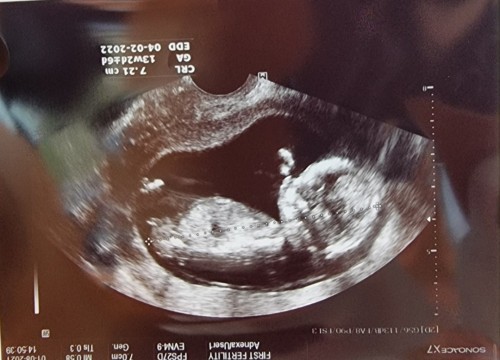

วันนี้มาอวดภาพตัวเล็ก ที่คุณหมอบอกตัวใหญ่ ดิ้นเก่งแล้ว ดิ้นโชว์ใหญ่เลย

บ้านนี้ก็กำหนดคลอดมีนา65ค่ะ น้องโตไวมาก แข็งแรงดี ตอนนี้คุณแม่ตั้งครรภ์ได้3เดือน เจาะเลือดเลือดตรวจโครโมโซม เช็คดาวซินโดรมผลออกมาน้องปกติ ความเสี่ยงต่ำค่ะ และรู้เพศเลย น้องเป็นผู้ชายค่า